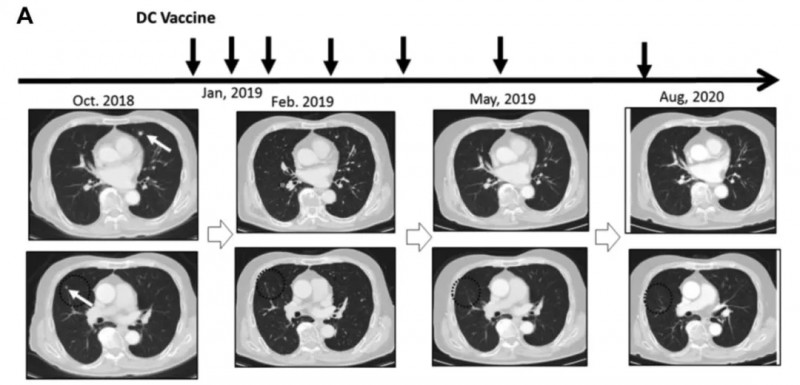

树突状细胞疫苗(DC疫苗)通过从患者体内提取DC细胞、负载特定肿瘤相关抗原(TAA)后回输,激发自身免疫系统对抗癌症。

《抗癌研究》杂志曾报道一项“新抗原肽脉冲DC疫苗单药治疗晚期实体肿瘤”的临床研究,多例患者治疗反应良好且无严重不良事件,其中一例肾细胞癌肺转移患者疗效尤为显著。

该患者2018年7月术后2个月出现多发肺转移,因肺静脉血栓无法使用靶向药,遂于2019年1月起接受新抗原肽脉冲DC疫苗治疗。

结果显示:接种3剂后获部分缓解(PR);接种6剂后接近完全缓解(CR),肿瘤基本消失;2020年8月复查CT,证实其维持持久完全缓解(CR)(详见下图)。

▲图源“Anticancer research”,版权归原作者所有,如无意中侵犯了知识产权,请联系我们删除